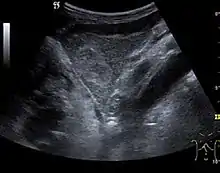

Liver cyst

Hydatid liver cyst. Diagnostic criteria are the presence of membranes and sediment inside.